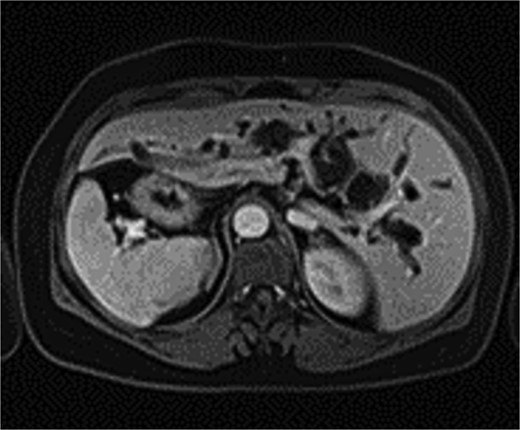

The patient, a 56-year-old female, was admitted on July 7, 2024, with a one-day history of abdominal pain and fever. The pain, which began on July 6 after consuming greasy food, was paroxysmal and located in the upper abdomen, accompanied by chills and a fever as high as 39°C. CT imaging revealed common bile duct stones and post-cholecystectomy status. Physical examination upon admission showed jaundice, with mild tenderness in the left upper quadrant, without rebound tenderness, and a negative Murphy’s sign. MRI and MRCP of the upper abdomen revealed bile duct dilatation due to a 26 mm stone in the distal common bile duct, with mirror-image arrangement of the internal organs (Figs. 1 and 2). The diagnosis was choledocholithiasis with cholangitis and situs inversus totalis. After completing preoperative evaluations, the patient underwent laparoscopic common bile duct exploration, choledochotomy for stone extraction, choledochoscopy, T-tube drainage, and lysis of adhesions under general anesthesia on July 9, 2024.

MRI shows a 26 mm stone in the distal common bile duct with bile duct dilation.